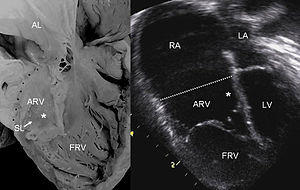

Pathological specimen and ultrasound image of a heart with Ebstein's anomaly: Abbreviations: RA: right atrium; ARV: atrialized right ventricle; FRV: functional right ventricle; AL: anterior leaflet; SL: septal leaflet; LA: left atrium; LV: left ventricle; asterisk: grade II tethering of the tricuspid septal leaflet